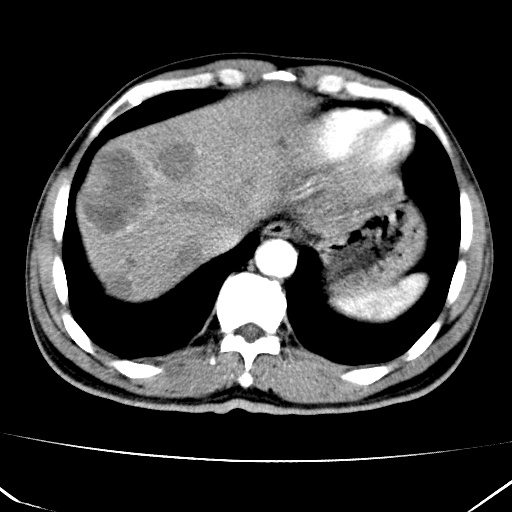

标题: CT17975:请求会诊。男、57岁。上腹部胀痛2天。临床诊断:糜 [打印本页]

标题: CT17975:请求会诊。男、57岁。上腹部胀痛2天。临床诊断:糜

肝脏多发类圆形低密度影,考虑肝脏转移瘤,肝胃韧带一淋巴结肿大,原发?胃癌?

考虑胃癌并肝脏及腹膜后淋巴结转移;不排除淋巴瘤。

肝内转移瘤,腹腔及腹膜后淋巴结转移。